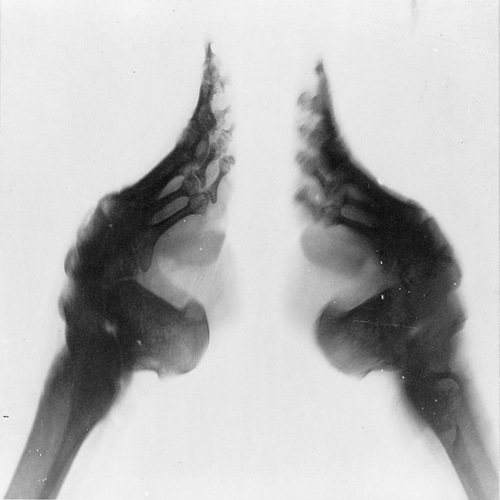

Шокиращата тайна на лотосовите стъпала

В Китай през периода на династията Сун (IX – XIII в.) се налага модата на малките стъпала Съвършеното стъпало, наречено „златен лотос“, е с дължина 7,6 см и се приема за едно от най-големите достойнства на жената, което обаче ѝ коства невероятни мъчения и я осакатява за цял живот. Оформянето му започва, когато момиченцето навърши 2-годишна възраст, тъй като костите му не …